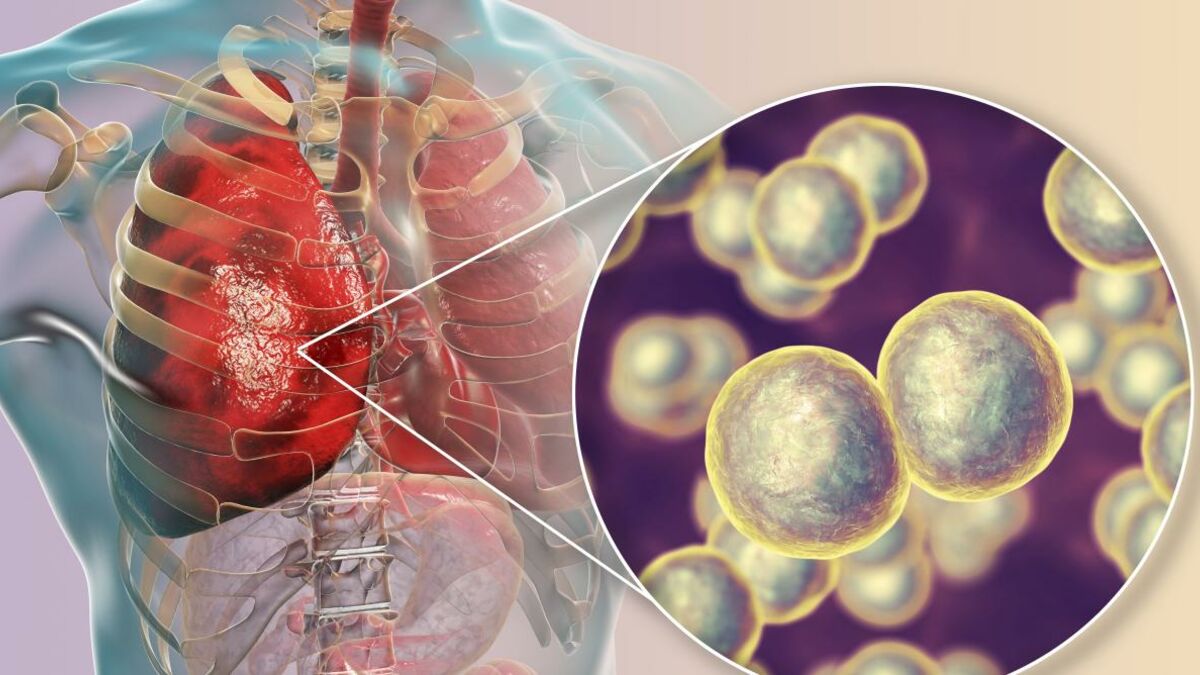

Фотографии бактерий, вызывающих бактериальные пневмонии у животных

Раздел: Другие животные